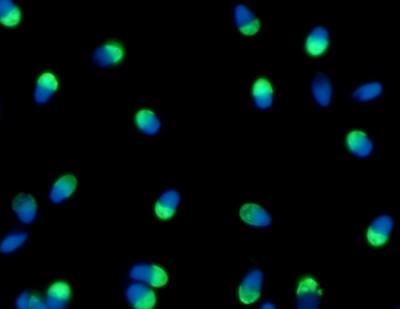

Espermatozoides humanos.

Créditos: Gentileza de la Doctora Vanesa Rawe